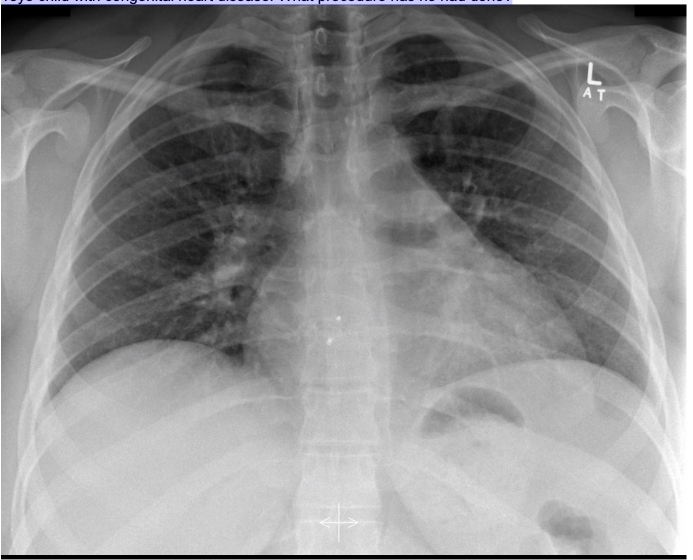

20.1 A 45-year-old man has poor oxygenation in the post anaesthesia care unit after a low anterior resection. His chest x-ray is below. The most likely diagnosis is

a) Left pneumothorax

b) Right pneumothorax

c) Left lower lobe collapse

d) Right lower lobe collapse

e) Normal XR

A

c

20.1 What is the abnormality in this CXR?

a. Pneumonectomy

b. Pleural effusion

c. Pneumonia

d. Unilateral pulmonary oedema

Complete white-out of left lung with air bronchogram sign consistent with total consolidation. Patchy areas of ground glass opacities in right lung. There is silhouetting of the left heart border and left hemi-diaphragm. There is no rib crowding to suggest atelectasis.

Complete white-out of the hemithorax with air bronchograms and trachea in a central position is consistent with consolidation secondary to pneumonia. The patient is on linezolid, micafungin, and piperacillin-tazobactam pending culture and susceptibility studies.

Differential diagnosis of hemithorax white-out with a midline trachea include:

- consolidation

- pulmonary edema/ARDS

- pleural mass

- chest wall mass

20.1 A 15-year-old boy undergoes a cardiac procedure for congenital heart disease. The intrathoracic device is a(n) (chest X-Ray shown)

a) AV repair

b) PV repair

c) ASD closure device

d) Parachute device

e) Right atrial appendage closure

device

Amplatzer Device